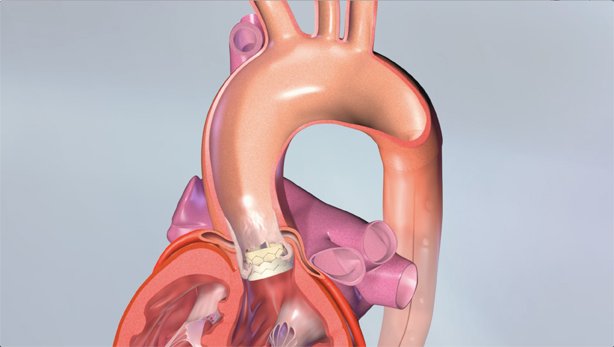

EnCompass F2 Device for cerebral embolic protection system in TAVR procedures

EnCompass Technologies

EnCompass’ F2 filter has pores small enough to block most emboli to the brain while preserving blood flow. During the TAVR procedure, 360-degree wall apposition of the filter in the aortic arch prevents migration. The filter, attached to a self-expanding, nitinol stent, is easy to insert, deploy and retrieve, according to the company. Copyright ©2021 KO Studios.